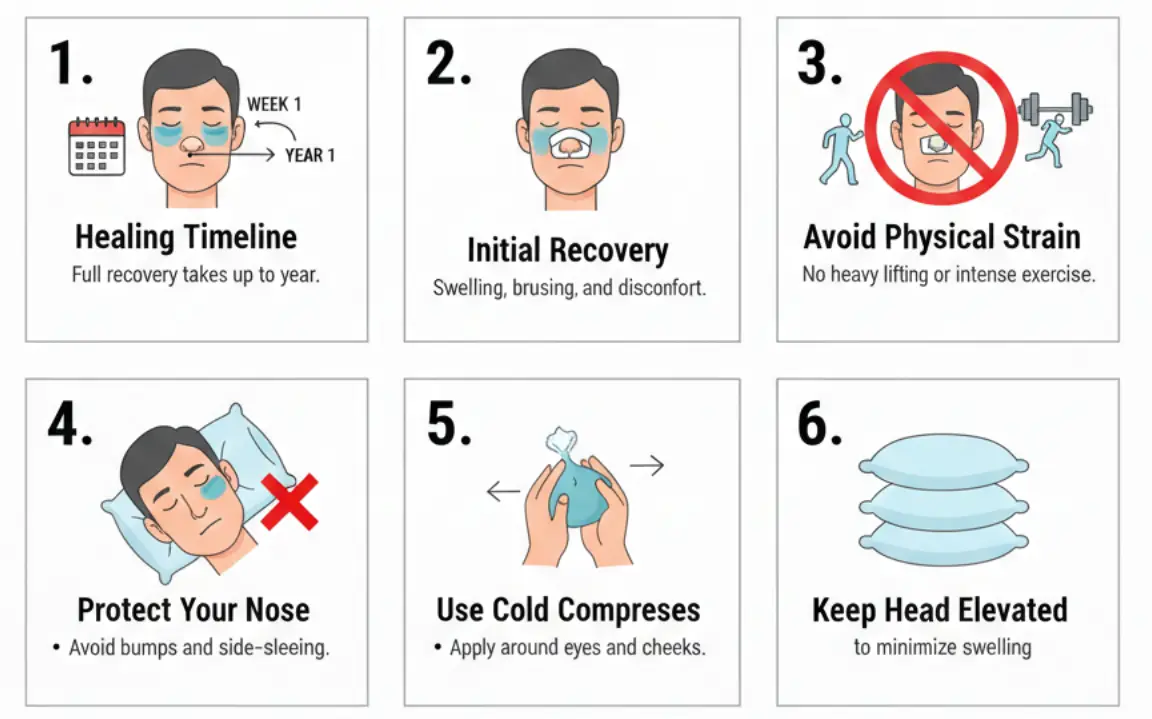

Recovery & Precautions:

Healing Timeline – Full recovery takes up to a year, though major swelling subsides within 4–6 weeks.

Initial Recovery – Expect swelling, bruising, and minor discomfort in the first few weeks.

Avoid Physical Strain – No heavy lifting, vigorous exercise, or sports for at least 4–6 weeks.

Protect Your Nose – Avoid any accidental bumps or pressure, including sleeping on your side.

Use Cold Compresses – Apply around the eyes and cheeks (not directly on the nose) to reduce swelling.

Keep Head Elevated – Sleep on your back with pillows to minimize swelling.